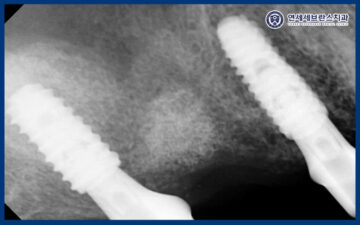

CT로 비교해 보았을 때,

상악동거상술을 통해

부족했던 상악동 하방 공간을 확보하여

임플란트 식립이 가능한 환경을

조성한 것을 확인할 수 있었습니다.